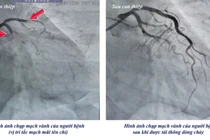

Kết quả chụp mạch vành cho thấy: động mạch vành trái trước (LAD) tắc hoàn toàn đoạn 1, động mạch mũ (LCX) xơ vữa, hẹp nhẹ, động mạch vành phải (RCA) hẹp 60–70% đoạn 2. Người bệnh được can thiệp đặt 1 stent động mạch LAD nhằm tái thông dòng máu nuôi tim.